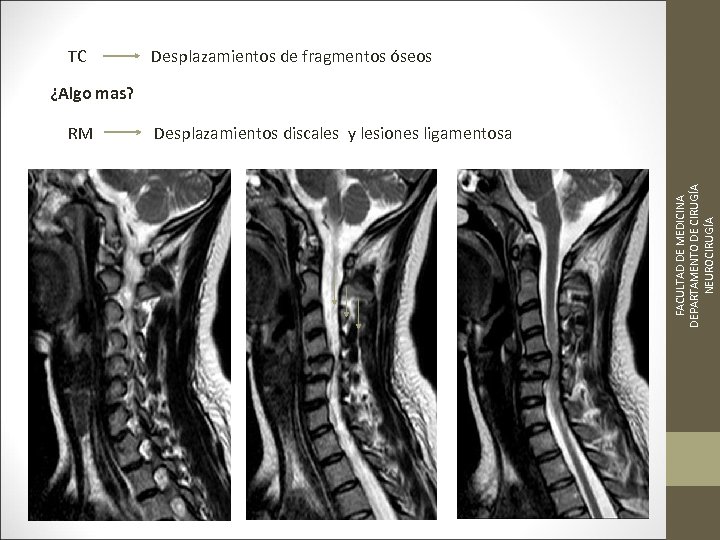

TC Desplazamientos de fragmentos óseos ¿Algo mas? FACULTAD DE MEDICINA DEPARTAMENTO DE CIRUGÍA NEUROCIRUGÍA RM Desplazamientos discales y lesiones ligamentosa